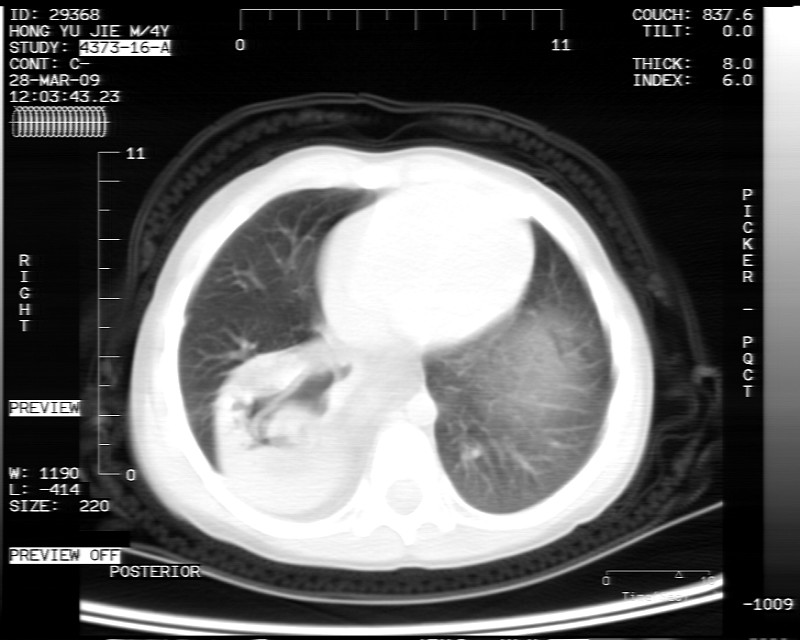

男性,3岁,斜疝术前常规检查胸片体检发现右下肺病变。咳嗽,无发烧。

内有气体,液平面,考虑食管裂孔疝可能性大。建议食道钡透。

有液气平面,前部肺纹理聚集(受压改变),周围肺野及相邻胸膜清晰,支持膈疝,可吞服造影剂看一下。

考虑膈疝(右侧胸腹膜裂孔疝?)。